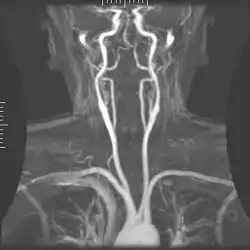

- استخدام الرنين المغناطيسي هو لغرض تشخيصي مثل تصوير الأوردة والشرايين، أو تصوير التغيرات العصبية في الدماغ، والرنين المغناطيسي يعتبر أفضل أنواع التصوير في توضيح الأنسجة وسوائل الجسم، وكذلك يستخدم لتخطيط الخطط العلاجية القائمة على العلاج الإشعاعي. قبل الفحص بالرنين المغناطيسي يجب مراجعة التاريخ المرضي والتأكد بشكل تام من عدم وجود جراحات سابقة أو حوادث أدت إلى تواجد معادن في الجسم مثل الشظايا، ويتم التأكد من ذلك عبر الفحص بالأشعة العامة الروتينية & مرور المريض من خلال كاشف معادن. يعطي المريض في الغالب صبغة خاصة تحقن في الجسم وذلك لزيادة التباين وتوضيح الأجزاء المتقاربة.

يستخدم هذا الجهاز في قياس التغيرات في الإشارات العصبية في الدماغ الناتجة عن تغيرات النشاط العصبي، وزيادة النشاط العصبي تؤدي إلى زيادة الاوكسجين الذي يتم استهلاكه، وبالتالي يعمل الجسم على زيادة نسبة الأوكسجين في الدم الأمر الذي يؤدي إلى زيادة نسبة الدم المشبع بالاوكسجين مقارنة مع الدم الغير مشبع بالأوكسجين. الدم المشبع بالأوكسجين والدم الغير مشبع بالأوكسجين يستجيبان بشكل مختلف للمجال المغناطيسي المتولد ومن خلال الاستجابتين المختلفتين يتم ملاحظة التغيير في النشاط العصبي.[6] أيضا يمكن رسم صورة ثلاثية الأبعاد للأوعية الدموية في النسج العصبية من خلال الاستجابتين المختلفتين لنوعي الدم.